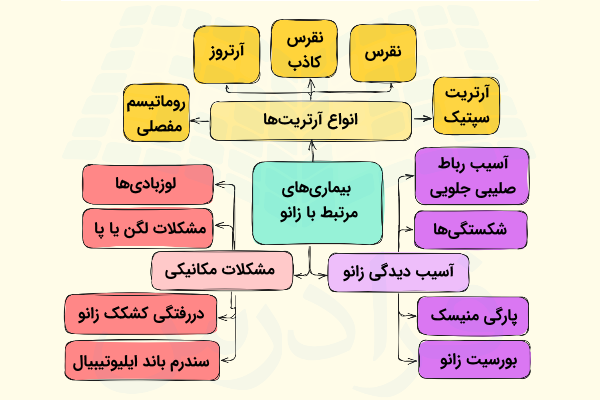

بیماریهای مرتبط با آناتومی زانو

زانو درد یکی از رایجترین شکایات افراد مختلف به خصوص در دوران بزرگسالی است که میتواند به دلیل فعالیتهای روزمرهای مانند راه رفتن، ایستادن یا نشستن بیش از حد و بلند کردن اجسام سنگین رخ دهد و به مرور زمان منجر به آسیب دیدن ساختارهای سازنده زانو مانند منیسکها، رباطها، غضروفها و غیره شود.

بیماریهای مرتبط با زانو میتوانند به دلیل عوامل ژنتیکی نیز ایجاد شوند، با توجه به این دو دلیل عمده یعنی سبک زندگی و ژنتیک، در ادامه با بیماریهای مختلف مرتبط با زانو به طور مختصر آشنا میشویم و یاد میگیریم که در هر بیماری چه بخشی از زانو متحمل آسیب گستردهتری میشود.

آسیب دیدگی زانو

آسیب رباط صلیبی جلویی

شکستگیها

پارگی منیسک

بورسیت زانو

مشکلات مکانیکی

بعضی مشکلات مکانیکی که میتوانند با درگیر کردن آناتومی زانو باعث تجربه زانو درد شوند که در ادامه آنها را نام برده و سپس توضیح میدهیم.

- «لوزبادی» (Loose Body) یا «اجسام آزاد داخل مفصلی» (Intra-Articular Free Bodies)

- «سندرم باند ایلیوتیبیال» (Iliotibial Band Syndrome)

- دررفتگی کشکک زانو

- مشکلات لگن یا پا

انواع آرتریتها

«آرتریت» (arthritis) یا التهاب مفصل انواع زیادی دارد، اما در این بخش به بررسی تمام آنها که بیش از ۱۰۰ نوع هستند نمیپردازیم و فقط تعدادی از رایجترین آنها را معرفی میکنیم.

- آرتروز یا «استئوآرتریت» (Osteoarthritis): رایجترین نوع آرتریت است که در طی آن غضروف موجود در زانو به دلیل استفاده بیش از حد یا افزایش سن آسیب میبیند.

- «روماتیسم مفصلی» (Rheumatoid arthritis): آرتریت روماتوئید یا روماتیسم مفصلی بیماری مزمنی است که میتواند اکثر مفصلهای بدن، از جمله مفصل زانو را تحت تاثیر قرار دهد.

- «نقرس» (Gout): نقرس نوعی التهاب است که در افرادی که رژیم غذایی پرپروتئینی دارند، شایعتر است. در حقیقت اختلال در متابولیسم پروتئین دلیل به وجود آمدن نقرس است و به طور معمول انگشت شست پا را درگیر میکند اما ممکن است زانو نیز درگیر نقرس شود.

- «نقرس کاذب» (Pseudogout): این بیماری ناشی از تشکیل کریستالهای حاوی کلسیم در مایع مفصلی است که خیلی وقتها با نقرس اشتباه گرفته میشود.

- «آرتریت سپتیک» (Septic arthritis): این بیماری نوعی عفونت باکتریایی است که همه مفاصل را درگیر میکند و میتواند آسیب گسترده ای در غضروف زانو ایجاد کند.